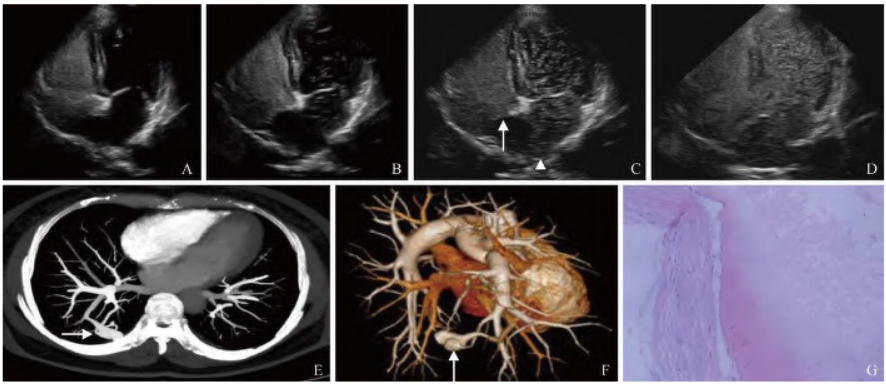

右心声学造影图像见图1A~D,经左肘静脉注射造影剂,右心顺序显影,5个心动周期后左心开始显影并逐渐呈云雾状,并见微气泡来源于肺静脉左心房入口;Valsalva动作后即刻左心房未见微气泡,5个心动周期后左心可见云雾状微气泡显影,左心显影持续至右心显影暗淡。右心声学造影检查提示:心脏右向左分流Ⅲ级,考虑肺动静脉瘘(pulmonary arteriovenous fistula,PAVF)。

胸部CT及肺动脉CT血管成像(图1E、F)检查提示:①右肺下叶后基底段动静脉畸形;②右肺中叶体积缩小。患者于全麻下行胸腔镜右肺楔形切除术。术中见:右肺下叶后基底段表面血管扩张变形,呈瘤样改变,切除后行肺修补术。病理检查(图1G)提示:右肺符合动静脉瘘改变。患者手术顺利,好转出院,随访复查头痛症状较前明显缓解,右心声学造影复查未见明显右向左分流。

图1 女,54岁,PAVF。右心声学造影示右心显影后第4个心动周期,左心未见显影(A);右心声学造影示右心显影后第6个心动周期,左心逐渐开始显影(B);右心声学造影示右心显影后第10个心动周期,左心可见大量微气泡,并见左心微气泡来自肺静脉左心房入口(箭头,C),左心微气泡并非来自房间隔(箭,C);右心声学造影示右心显影后第15个心动周期,左心可见云雾状微气泡(D);CT肺动脉横断位重组示右肺下叶后基底段结节状畸形血管影(箭,E);肺动脉三维重建示右肺下叶后基底段畸形血管,可见供血动脉及粗大引流静脉(箭,F);病理示右肺符合动静脉瘘改变(HE,×100,G)